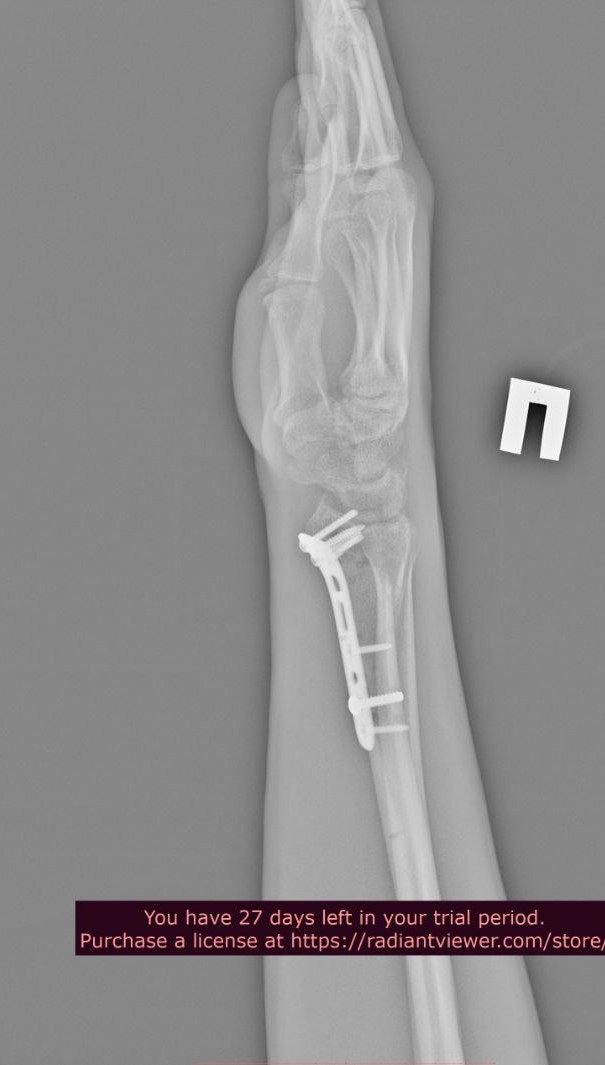

Добрый день. Два года назад упал с большой высоты, из-за чего мне установили металлоконструкции в плечевой и локтевой костях левой руки и в лучевой кости правой руки. Снимки ниже. Также имеются ограничения кисти на правой руке (из-за наличия пластины в лучевой кости), она разгибается максимум на 60 градусов из 90. Также, локтевая кость не разгибается до конца на пять градусов (что несущественно, но факт есть). Хотел бы уточнить, имею ли я возможность в моей ситуации получить категорию "В"? Спасибо.

Лучевая кость